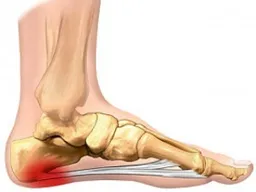

Por que ele resolve dar as caras justo no seu calcanhar? Geralmente, é uma resposta a um esforço repetitivo ou a uma sobrecarga nessa região. Atividades que exigem muito impacto, como correr ou ficar muito tempo em pé, podem ser gatilhos. Além disso, um tipo de pisada incorreta, sapatos inadequados (sem amortecimento ou muito apertados) e até o excesso de peso contribuem para que essa tal de fáscia plantar fique inflamada e, com o tempo, o esporão se forme. É o corpo pedindo socorro, de certa forma.

O mais importante é entender que nem sempre o esporão causa dor. A dor que você sente é, na verdade, uma inflamação na fáscia plantar. O esporão é só uma consequência. Mas quando a dor aparece, ela costuma ser mais forte pela manhã, ao dar os primeiros passos, ou depois de ficar um tempo sentada e levantar. O alívio nem sempre é imediato, mas com os cuidados certos, dá pra controlar e viver sem esse incômodo. Vamos cuidar desse calcanhar!

Essa dor nada mais é do que uma inflamação na fáscia plantar, que é aquele tecido que liga o calcanhar aos dedos do pé. O esporão em si é um depósito de cálcio que se forma nessa região. Com o tempo, ele pode irritar os tecidos ao redor, causando esse desconforto.